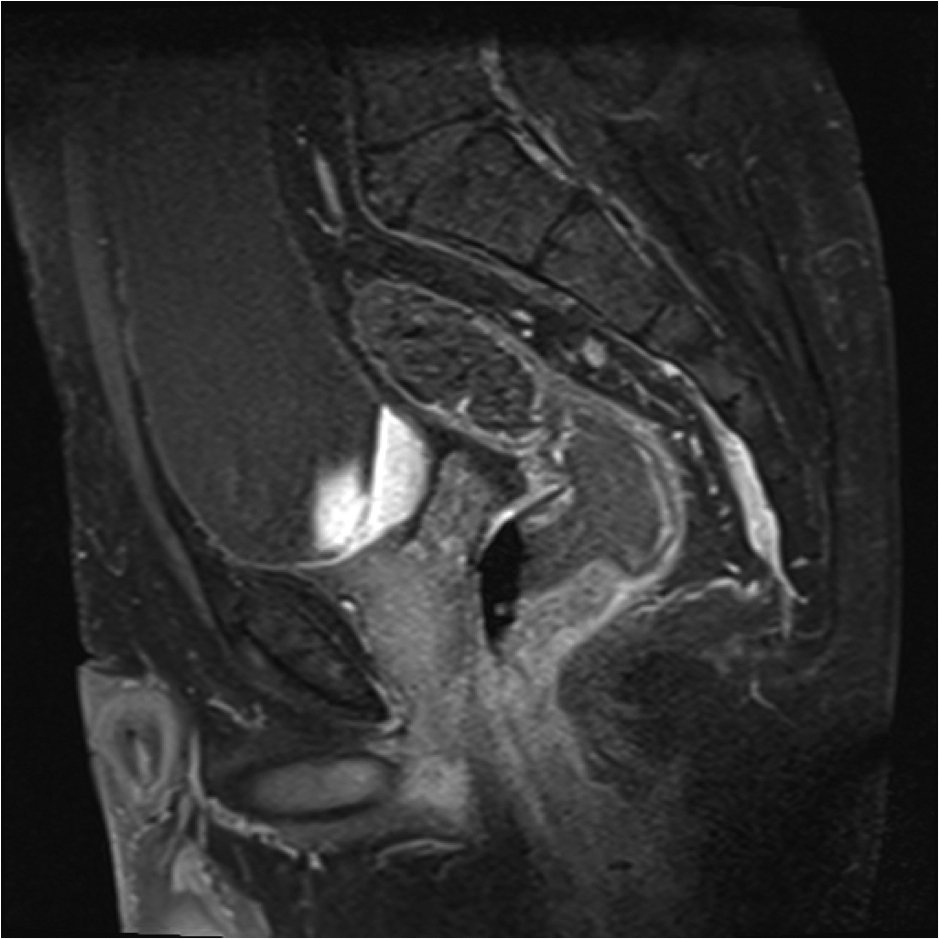

Fig1. Pacient cu neoplasm rectal stadiul IIIC (T3; N2; M0) confirmat bioptic, adenocarcinom mixt G2

a-d imagini T2 ponderate în plan sagital, oblic axial și oblic coronal – masă tisulară dezvoltată superior de joncțiunea anorectală, lateral dreapta, cu minimă extensie la nivelul grăsimii mezorectale și limfoganglioni mezorectali cu diametru de până la 10 mm;

e,f) restricție de difuzie la nivelul tumorii rectale și a doi ganglioni mezorectali

g,h,i) priză de contrast moderată la nivelul tumorii rectale și al ganglionilor mezorectali

j) reconstrucții curbe în planul adevărat al rectului, cu evidențiere mai bună a fasciei mezorectale